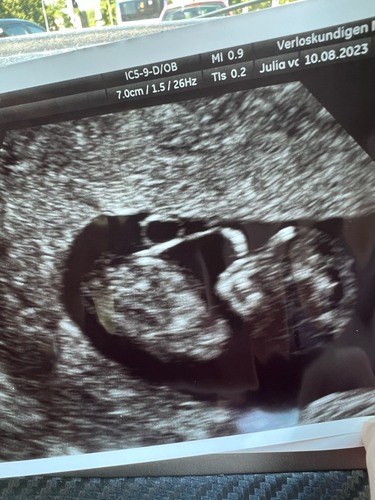

Ik kan er ook geen wijs uit worden…. Zien jullie hier wat in?

Hele moeilijke dit..

Ik zou gaan voor een meisje, minder dan 30 graden tov ruggenwervel. Ben heel benieuwd!

Ik denk ook meisje